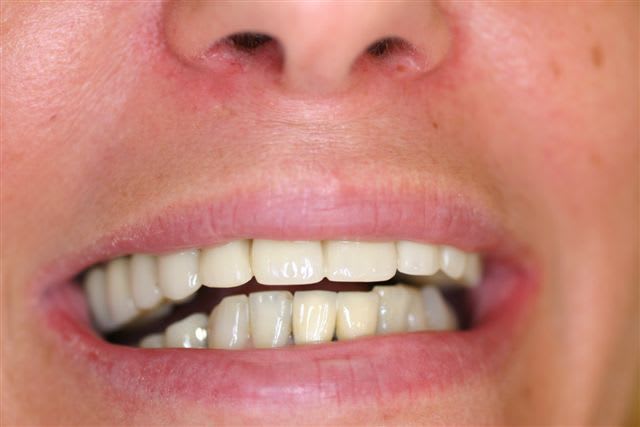

5 Un bridge transitoire a été mis en place deux jours après la pose des implants

et roule mais pour la pérennité du cas une équilibration due l'ensemble de la bouche .....